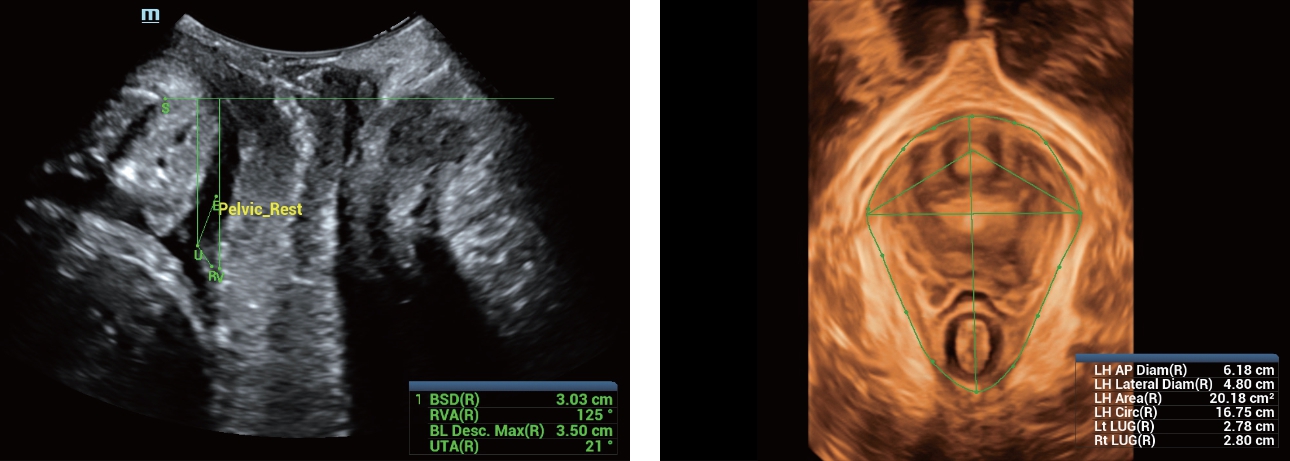

Además de la calidad de imagen de primer nivel, Resona?7 también mejora las capacidades de investigación clínica con el revolucionario V?Flow para la evaluación hemodinámica vascular y con la adquisición de planos más inteligente a partir de conjuntos de datos 3D para el diagnóstico del SNC fetal. Al combinar el funcionamiento multitáctil basado en gestos más intuitivo y todas las características clínicas esenciales, Resona?7 realmente lidera las novedades en innovación de ecografías.